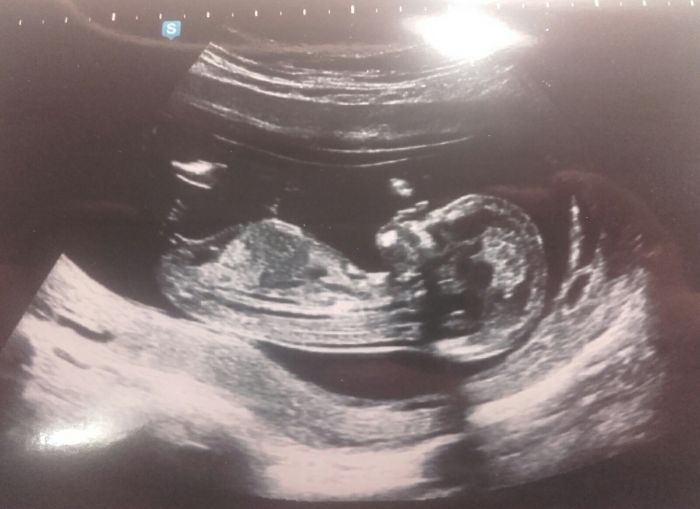

Dneska jsem byla na screeningu a je všechno v pořádku, mám velikou radost. Toto je naše láska

Minnie - to je krásná fazolka, užívej, doufám, že brzy budu v ruce držet taky takovou fotečku